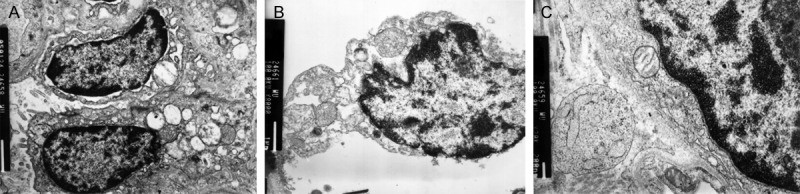

Ultrastructural change of lung tissue

In sham group, normal pathological including rich microvilli, mitochondria and reticulum was observed and the alveolar epithelial walls were well maintained (Figure 6A). Figure 6B was the representative slide from the CPB group demonstrating obvious lung injury marked alveolar epithelial cell shedding, matrix exposure, vascular congestion, mitochondria of epithelial cells swelling obviously. In DOX treated group, the pathologic changes were improved significantly. The alveolar epithelial walls were relatively maintained and the desmosomes and microvilli were observed, and the mitochondria and reticulum increased in cytoplasm (Figure 6C).

Figure 6.

Ultrastructure change of lung tissue. A. Sham group demonstrating normal pathological and the alveolar epithelial walls were well maintained. B. Representative section from CPB group demonstrating lung tissue obvious injury marked alveolar epithelial cell shedding, matrix exposure, vascular congestion, mitochondria of epithelial cells swelling obviously. C. DOX treatment group demonstrating lung tissue injury was improved and the alveolar epithelial walls were relatively maintained.